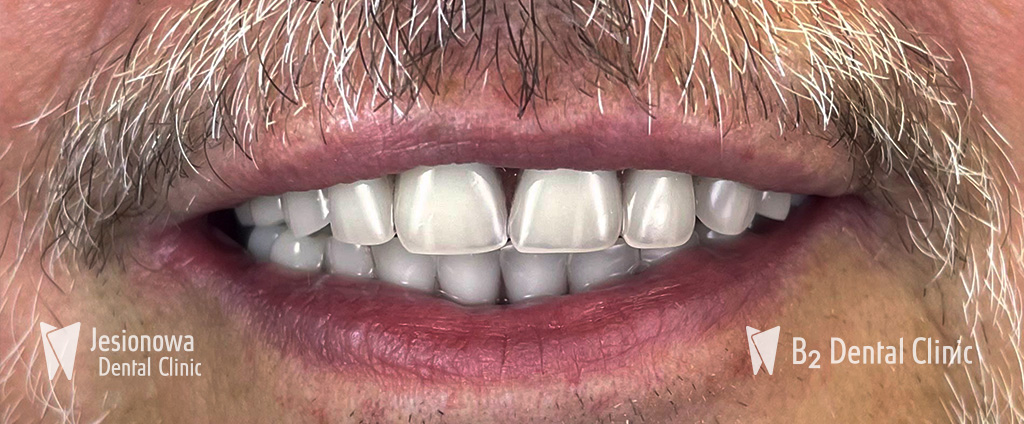

5. Oddanie pracy

Ostatnim etapem 1 dniowej wizyty jest założenie Twoich nowych zębów i przymocowanie ich do implantów. Odzyskasz zdrowy i piękny uśmiech w tym samym dniu (dotyczy mostów tymczasowych).